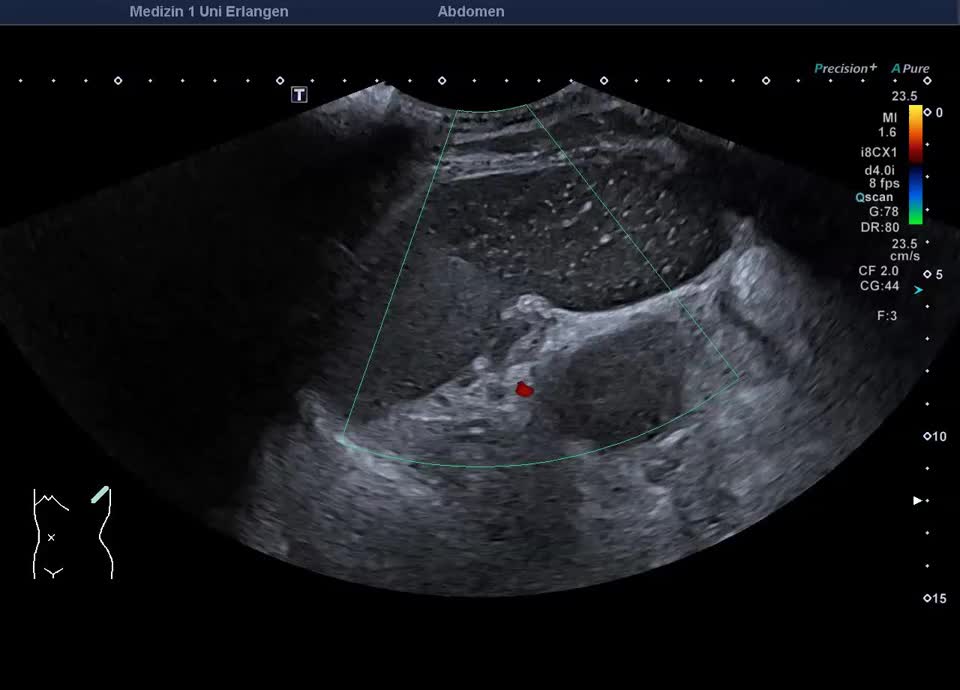

Epikrise: 19-jährige Patientin mit einem schweren angeborenen Herzfehler berichtet über plötzlich aufgetretene starke Schmerzen in der linken Flanke vor 14 Tagen. Sonographisch zeigt sich die Milz regelrecht lokalisiert, mit einem ausgedehnten Milzinfarkt der unteren Milzhälfte. Weder im Farbdoppler, noch im CEUS, lässt sich eine Restperfusion der unteren Milzhälfte feststellen. Therapeutisch wird eine Antikoagualtion begonnen und eine Verlaufskontrolle in 4 Wochen veranlasst.